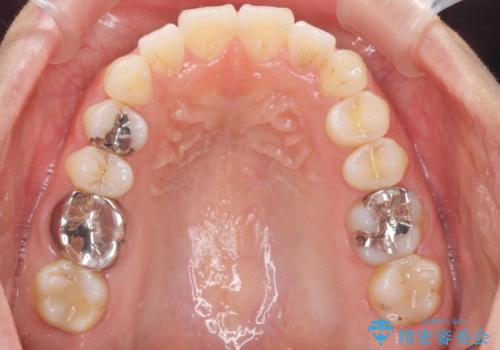

前歯の角度を改善するマウスピース矯正

しっかりと拡大を行い、IPRも併用したことで歯並びと前歯の角度を大幅に改善することができました。

- 前歯の角度・重なりの改善を求めて矯正治療を希望され来院されました。

通常このような場合、小臼歯を4本抜去しワイヤー矯正を行う治療計画も検討されますが、今回は側方に拡大できる骨量が十分に存在したため抜歯をしない矯正治療の計画を立てます。